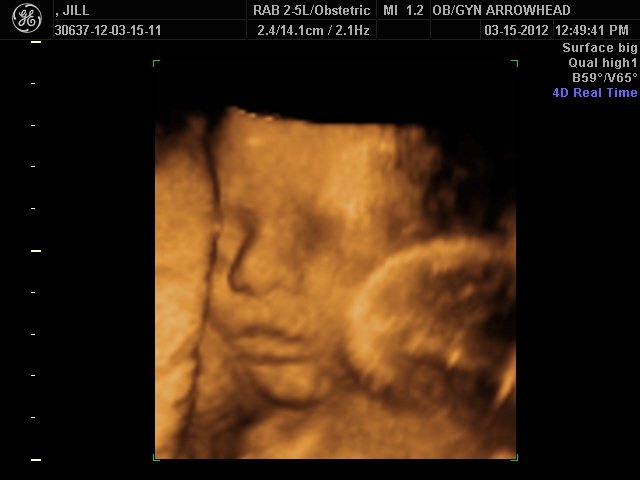

We offer complimentary 3D/4D Ultrasounds to all our OB patients around 30 weeks! The following photos are some examples of our work, shown with permission from our patients.